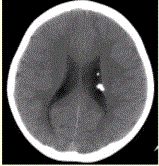

问题 患者男,20岁,面部皮脂腺瘤,头CT显示如下图。 该病伴有的相关异常不包括

选项 A.肾血管平滑肌脂肪瘤 B.心脏横纹肌瘤 C.其他实质器官的腺瘤、平滑肌瘤等 D.所有患者均会出现三联征 E.皮肤(面部)纤维血管瘤

答案 D